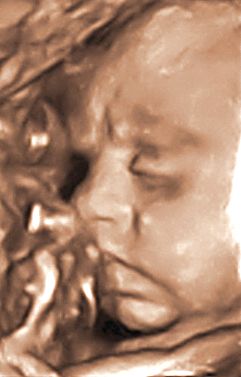

Сегодня были на третьем,заключительном УЗИ-скрининге! Эмоции переполняют.

Так приятно наблюдать за тем,чем твоя кроха занимается внутри тебя! Ну и конечно же,в очередной раз убедиться в здоровом развитии ребеночка! Все у нас хорошо, внешне-КОПИЯ папа:ямочка на подбородке,форма носика.пухлые губки и "ежик" на голове.

Только вот,что-то сегодня мы были не в очень хорошем расположении духа,все время отворачивали мордашку,упирались носом в стенку плаценты,ручками прикрывались,но все же потом перестали сопротивляться и показались.Но...на фото получились с нахмуреными бровями и надутыми щеками!